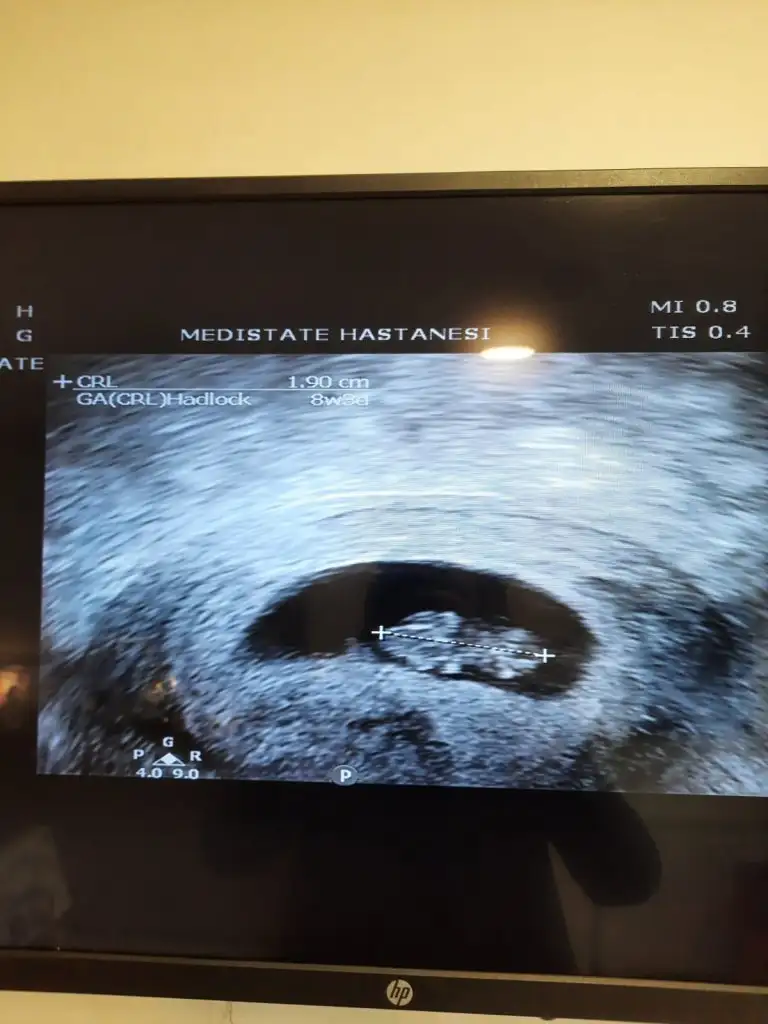

8+3 vajinal ultrasonSelam Kızlarbir çok kişi gruplardan beni bilir. Yine yetiştim imdatlara

Yok canım bilmediğimden soruyorum öyle görmek istediğimden değil. Bak birlikte oldukları fotoda üstteki sol olmuyor mu? Çok anladığım işler değil neye göre sağ/sol bilmiyorum zatenİlk fotoyu attığımda tek kese vardı ve erkek demiştin. Bugün gittim bi de ne göreyim çift keseVajinal ultrason biri 7+1 diğeri 6+6. Üstte sonradan beliren kesedeki bebiş solda gibi

Kuzum o yatay duruyo sanırım kese uzun ince o yıldızlı alanlarda heralde baştan ayağa uzunluğu öyle demisti doktorkuzum bebek sence sağda mı solda mı? farkındaysan iki yanda da yıldızlı alan varo yüzden yanlış yorum yapmak istemedim

evet kuzum öyle zaten de önemli olan bebek kafası?Kuzum o yatay duruyo sanırım kese uzun ince o yıldızlı alanlarda heralde baştan ayağa uzunluğu öyle demisti doktor